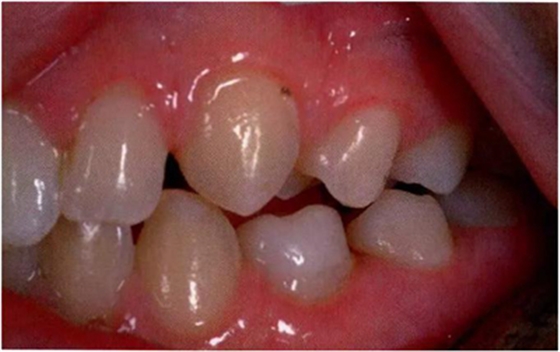

圖1:輕度下沉的臨床像

圖2:中度下沉的臨床像

圖3:重度下沉的臨床像